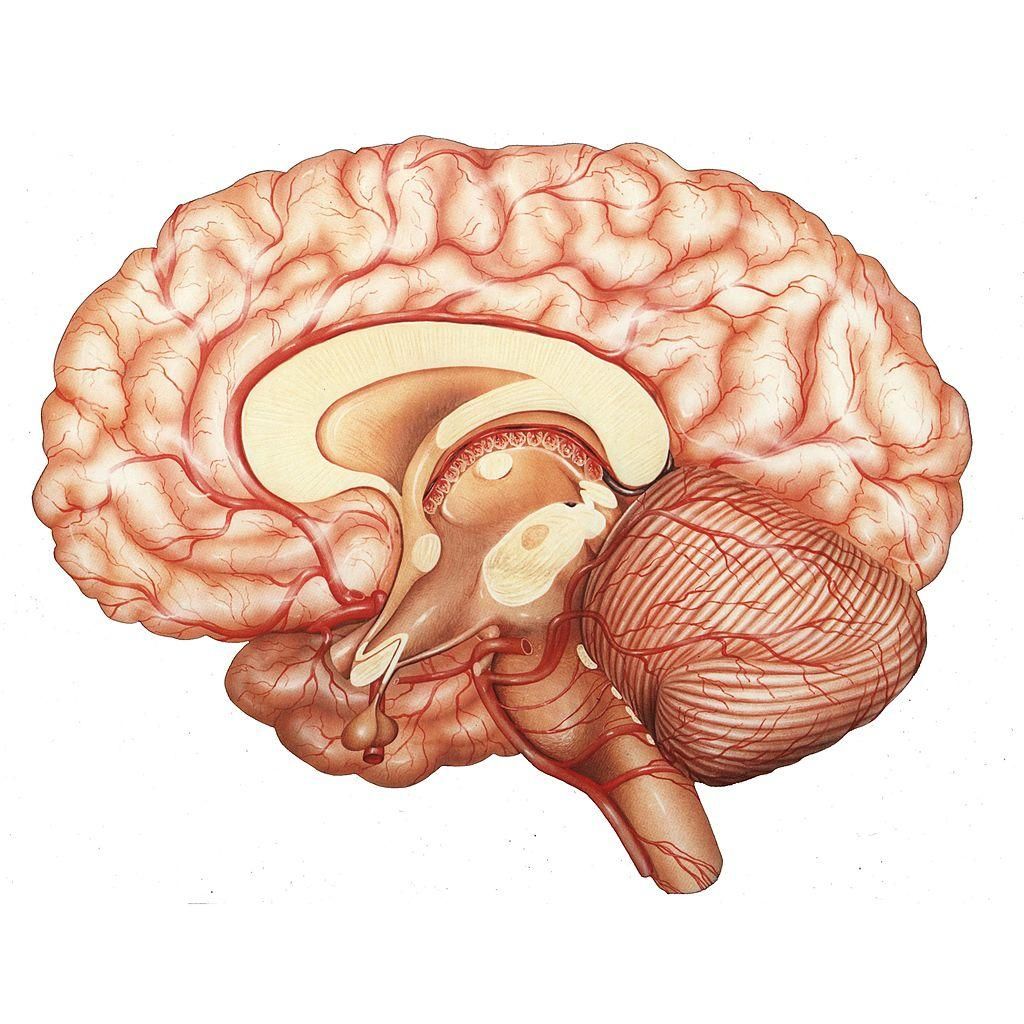

Il cervello è l’organo più complesso e meraviglioso del nostro corpo. Tuttavia, è una struttura misteriosa ed è avvolta da numerosi equivoci e bufale.